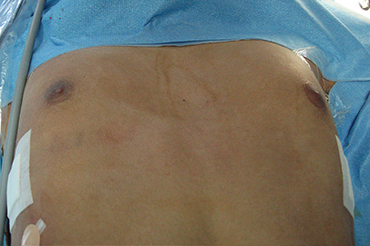

Pectus Excavatum